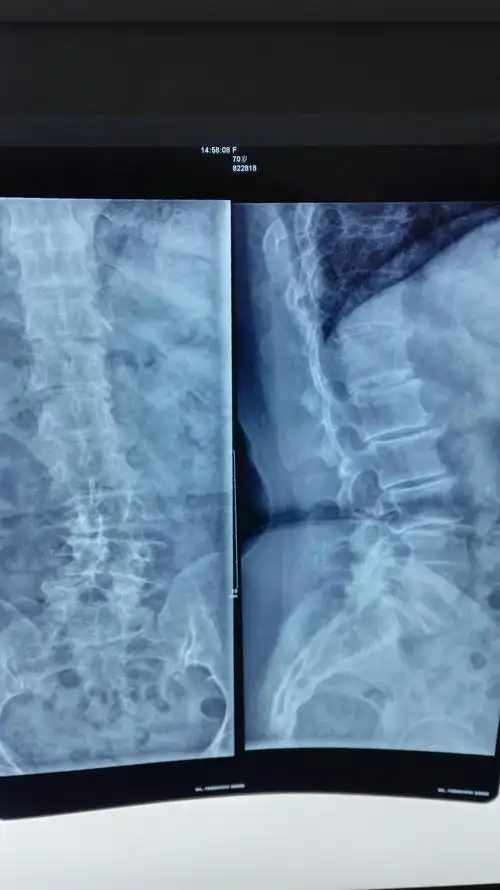

术前x线正位片

患者的腰椎x线片